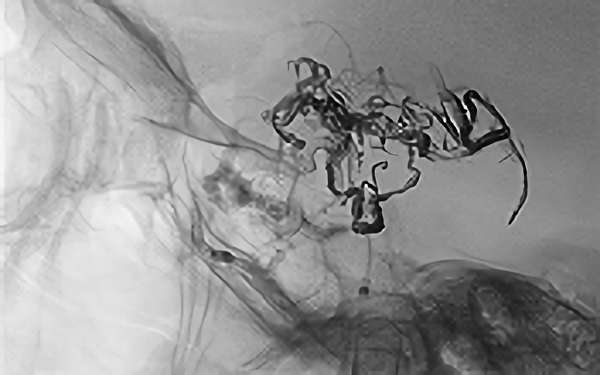

No.1620 手術前

No.1620 手術中